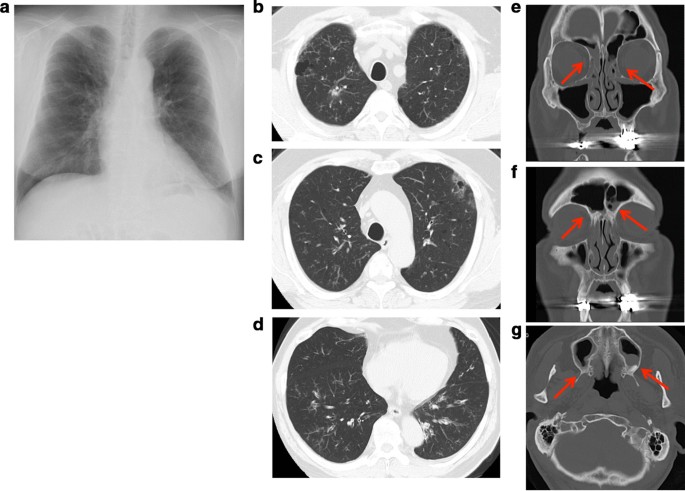

The patient experience his first bronchial asthma attack at 22 cycles of nivolumab treatment and was treated with a short course of corticosteroid burst therapy with 20 mg prednisolone along with inhalation therapy with budesonide/formoterol fumarate. This bronchial asthma attack was thought to be an adverse event associated with nivolumab; however, the patient continued the same dose of nivolumab treatment until 37 cycles because a good response against the kidney neuroendocrine carcinoma had been achieved. This clinical course is summarized in the Additional file 1: supplementary figure. Although nivolumab treatment had been discontinued until 37 cycles, the absolute eosinophil count remained high (26.6%, 1782.2 cells/μL) and his serum immunoglobulin E (IgE) levels were increased (924 IU/mL). Titers of anti-nuclear antibodies and anti-neutrophil cytoplasmic antibodies remained in the normal range. An IgE-radioallergosorbent test detected normal IgE levels, except against Japanese cedar and white cedar pollen. His fractional exhaled nitric oxide level was elevated to 107 ppb (normal range: 15–37 ppb). The patient had no history of allergy: however, all of his children had allergic bronchial asthma. He also showed dyspnea on exertion, developed sputum, and exhibited swelling and pain in his bilateral fingers. There were no other physical findings, including wheezing. Chest X-ray and computed tomography (CT) scanning detected a bilateral linear shadow which was not detected at his first visit to our hospital (Fig. 1a–d), and paranasal sinus CT scanning showed inflamed ethmoid, frontal, and maximal sinuses, indicating sinusitis (Fig. 1e–g). Although he had a normal respiratory function before initiating nivolumab treatment (FEV1.0 = 3.08 L, FEV1.0/FVC = 71.0%), his respiratory function test indicated an obstructive ventilation disorder (FEV1.0 = 1.63 L, FEV1.0/FVC = 50.6%). These results suggested that he had either eosinophilic pneumonia or EGPA. To confirm our hypothesis, we performed a bronchoscopy; the bronchoalveolar lavage fluid collected from the right B5 contained 40% lymphocytes and 3% eosinophils. Histopathological examination of a transbronchial lung biopsy sample from the right B8 showed small blood vessel hyperplasia with neutrophil infiltration and thickening of the alveolar septa with prominent eosinophil infiltration. Large numbers of red blood cells were observed on the lung tissue along with intra-alveolar bleeding (Fig. 2a, b), suggesting distinct alveolar hemorrhage with eosinophilic pneumonia. However hemosiderin-laden macrophages were not detected by Berlin blue staining, suggesting that the alveolar hemorrhage was an occasional event. Because he had experienced several bronchial asthma attacks and was already being treated with medication, the representative clinical findings needed for the bronchial asthma diagnosis were likely masked. To confirm the pathological findings of bronchial asthma, transbronchial mucosal biopsy was conducted. A bronchial mucosal lesion of the secondary carina also showed smooth muscle hyperplasia and thickening of the basement membrane with eosinophil infiltration (Fig. 2c). These findings suggested that the patient had bronchial asthma, eosinophilic pneumonia, and small vessel vasculitis. Finally, nerve conduction analysis showed that his right ulnar nerve conduction velocity was slightly decreased. There were no brain metastatic diseases, cervical spondylosis, or abnormalities related to rheumatoid arthritis. Although we could not definitively diagnose his neurological abnormalities, EGPA was thought to be one cause of the neuropathy. According to these findings with small vessel vasculitis, the patient was diagnosed with EGPA as per the American College of Rheumatology criteria for EGPA [5]. Distinct alveolar hemorrhage was not severe in the clinical setting and no heart involvement was detected; thus, treatment with 20 mg/day oral prednisolone was started. After 3 months, his bronchial asthma was improved, and bilateral infiltration had disappeared, as shown in Fig. 3. Steroid therapy was gradually tapered; during its discontinuation to less than 10 mg/day, a biweekly dose of mepolizumab (300 mg/day) was started to treat the EGPA. Currently, the patient is being treated with both nivolumab and mepolizumab, his peripheral eosinophilia has almost disappeared, and his respiratory function has improved (FEV1.0 = 2.94 L, FEV1.0/FVC = 71.2%), with paranasal sinus CT scanning showed normal findings (Fig. 3) after a year of treatment. He appears to be stable except for his neuropathy; to date, there have been no bronchial asthma attacks or CT scan abnormalities (Fig. 3).

Thoracic radiogram and computed tomography (CT) scan at the bronchoscopy exam. Chest radiogram (a) showed bilateral linear shadow. Thoracic CT scan of upper (b, c) and lower lobes (d) showed bilateral ground-glass opacity. e–g Paranasal sinus CT scan; Ethmoid sinus (e), frontal sinus (f) and maxillary sinus (g). Each arrow indicates nasal mucosa thickening and fluid collection in the sinus. These appearances suggest paranasal sinusitis